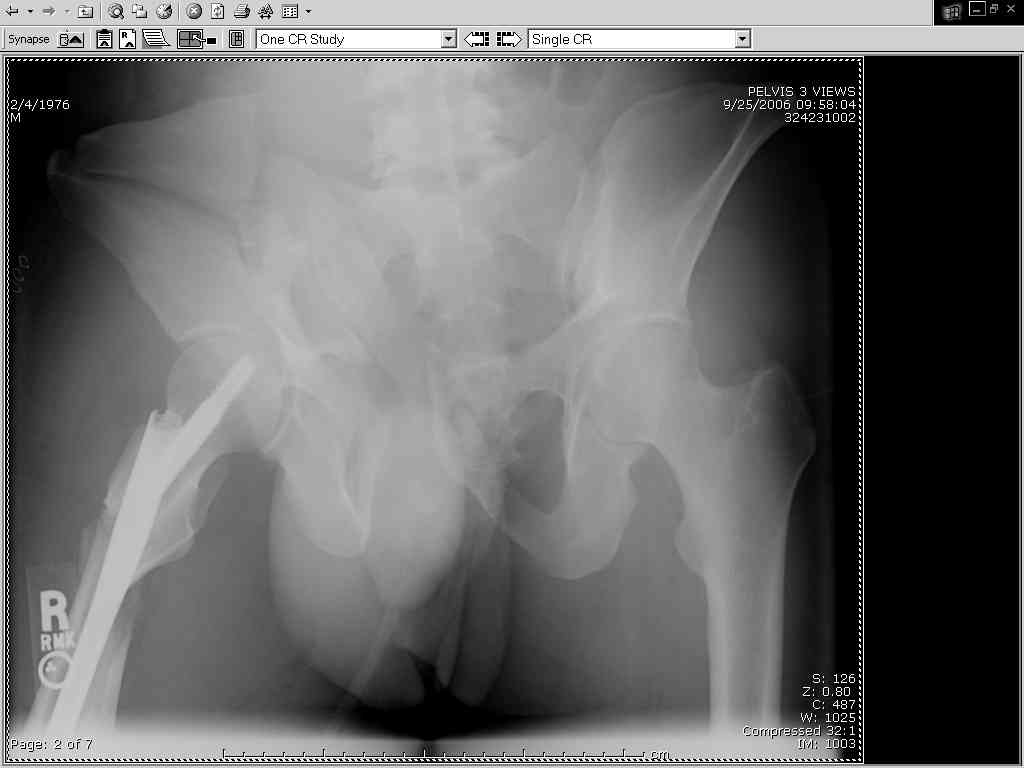

Thanks Adam - I agree it's not a pure APC (is there really such thing as a pure force vector strictly in the x,y or z plane?). I stand corrected. Maybe a hybrid APC (ext rot of L hemipelvis, symphysis disruption, ext rot of R anterior innominate) plus vertical shear as well with 3 or-so cm of cephalad migration of the R ilium. Maybe just "C-type".....

It almost looks to me like an extra-articular both column fx, in addition to the pelvic component. It has the typical triangular fragment and the OO view has a hint of the spur. You may be able to get it all with plates. I would consider fixing the crest first, then a long plate for both symph and iliac portion. SI may close with reduction of symphisis. Looks like the inferior portions are intact. I like your plan as well. You will probably solicit lots of opinion. Good luck. Look forward to post op view.

My current plan is supine, ORIF symphysis with as close to AFT reduction as possible, then fix the R ilium via lat window Ilioing.

approach with lags in the solid crest bone, 2 plates (one along pelvic brim and one up on the inside of the crest), then, if I have good posterior reduction and can get a good view of the ICD on my lat sacral view with image, L side perc SI screw, if not then anterior L SI approach and 2 anterior plates.